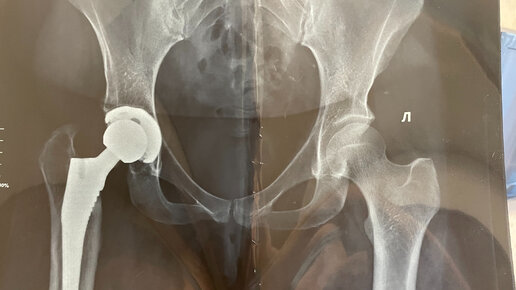

Всем добрый день! Сегодня я решила написать немного необычную статью для моей странички, это рассказ про эндопротезирование тазобедренного сустава. Дело в том, что в августе 2020 года я прошла этот путь, от подготовки к операции до полного восстановления, но на этапе ожидания своей очереди по КВОТе, я много читала и готовилась морально, а информации "из первых уст" в сети было крайне мало, поэтому, уверена, что смогу кому-то ответить на вопросы и может даже подбодрить. Пожалуй, начну свою историю с самого начала...

Эндопротезирование тазобедренного сустава по КВОТе, подготовка к операции и реабилитация. Роды после эндопротезирования.